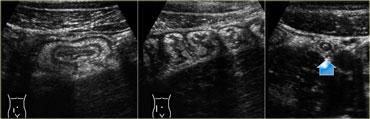

Hình ảnh siêu âm của viêm túi thừa phụ thuộc vào giai đoạn của bệnh.

Ở giai đoạn sớm nhất, thường có dày thành đại tràng khu trú, ban đầu chưa mất cấu trúc lớp nhưng sau đó sẽ mờ dần cấu trúc lớp tại chỗ.

Xung quanh sỏi phân là mô tăng âm, không nén được, đại diện cho mạc treo và mạc nối đang viêm cố gắng bịt kín vị trí sắp thủng.

Lớp mỡ viêm này, được xác định rõ nhất khi nén ép nhẹ nhàng và ngắt quãng bằng đầu dò, là dấu hiệu bắt buộc để chẩn đoán viêm túi thừa (15).

Ở hơn 80% bệnh nhân, sau một hoặc hai ngày, mủ và sỏi phân được thoát ra vào lòng đại tràng thông qua sự suy yếu khu trú của thành đại tràng tại vị trí cổ túi thừa ban đầu (Hình).

Tương ứng với đó, các triệu chứng của bệnh nhân thuyên giảm.

Cần lưu ý rằng các thay đổi viêm tồn dư (giai đoạn R) có thể tồn tại trong thời gian dài sau khi thoát dịch, do đó bệnh nhân có thể hoàn toàn không có triệu chứng trong khi vẫn còn các bất thường đáng kể có thể quan sát được trên siêu âm.

TRÊN: Siêu âm cho thấy dày thành đại tràng sigma tại vị trí túi thừa đang viêm (mũi tên) chứa sỏi phân (giai đoạn 0).

Lưu ý mô tăng âm, không nén được xung quanh đại diện cho mạc nối và mạc treo đang bao bọc hiệu quả vị trí sắp thủng.

Trong lớp mỡ, có thể thấy các dải giảm âm dạng tuyến tính (đầu mũi tên).

GIỮA: Một ngày sau, bệnh nhân cảm thấy khá hơn một chút.

Sỏi phân không còn nhận diện được rõ ràng và nội dung túi thừa đang phình ra phía lòng đại tràng sigma, dấu hiệu của sự thoát dịch sắp xảy ra.

DƯỚI: Hai ngày sau đó, bệnh nhân gần như không còn triệu chứng.

Mủ và chất phân đã thoát hoàn toàn vào lòng đại tràng sigma, để lại một túi thừa rỗng (mũi tên cong).